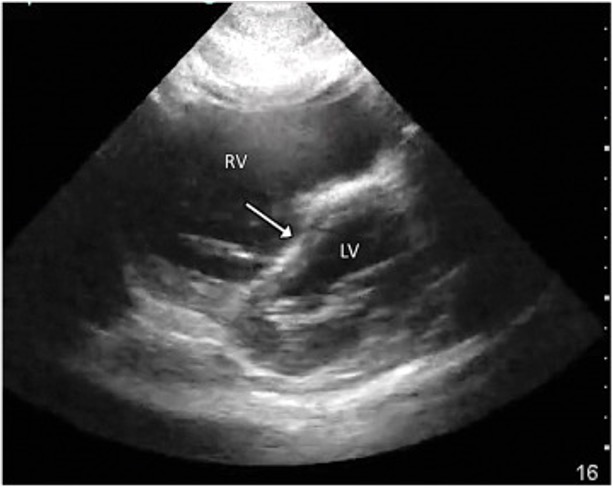

Septal Flattening (“D sign”)

McConnell Sign